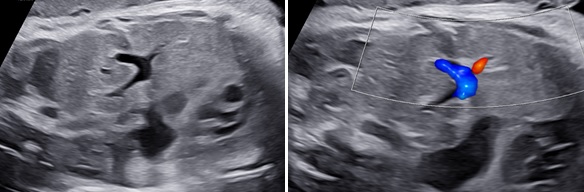

Thoát vị hoành phải nếu chỉ đơn thuần gan lên có thể khó nhận diện vì phản âm của gan tương tự phổi trên siêu siêu âm thang xám. Hình ảnh đường mật, túi mật là đặc trưng giúp nhận diện gan. Doppler màu có gía trị vì giúp nhận diện các tĩnh mạch gan. Dấu hiệu gián tiếp có thể thấy là hình ảnh trục tim bị lệch.

3. Hình ảnh tĩnh mạch rốn đoạn chia nhánh ra tĩnh mạch cửa trái trên Doppler màu trong mặt cắt ngang tại vị trí chu vi bụng cong về phía bên trái gợi ý thoát vị gan

Hình 7. A, Mặt cắt đứng dọc bụng thai nhi và lồng ngực thể hiện thoát vị gan trên thang xám và Doppler cho thấy ảnh gan thoát vị với các mạch máu gan bên trong